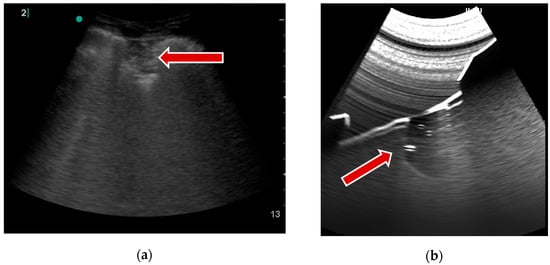

B-lines, on the other hand, are vertical lines that represent thickened or edematous lung interstitial spaces and are commonly associated with pulmonary edema or interstitial lung diseases. To simulate this artifact, the intensity of the response is randomly increased at the pleural line, leaving a bright trail interpreted as a B-line. A pseudorandom value is calculated from the UV map (rendered in the previous step) for each ray of the ray marching algorithm. Then, a strength parameter associated with the patient’s landmark determines the visibility of the B-lines. This parameter ranges from 0 (no B-lines) to 1 (multiple coalescent B-lines). Radial blur, added in the final step, increases visual similarity to real artifacts. An example of that artifact results is visible in Figure 4.

Figure 5. Pleural break example: (a) real examination [18]; (b) the LUS simulation.